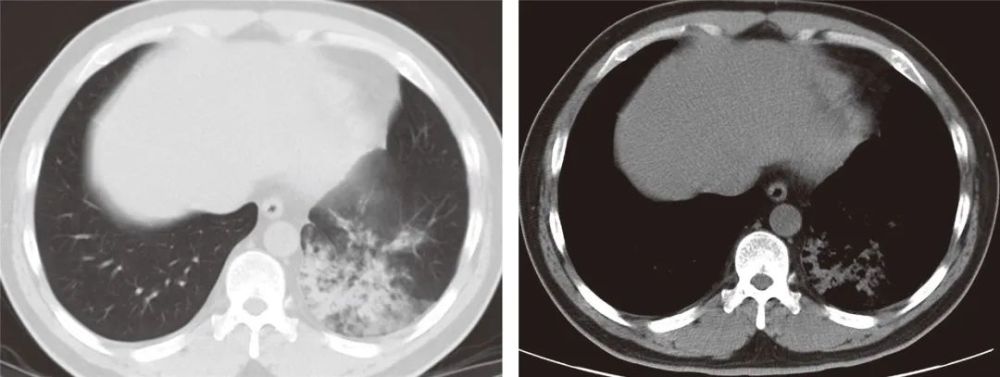

患者男,49岁,逗留3 d,5 d后发病,双肺多发磨玻璃密度影为主伴有实变

a 入院时胸片无异常.b 胸片显示新发左肺门实变(肺浸润迅速发展).